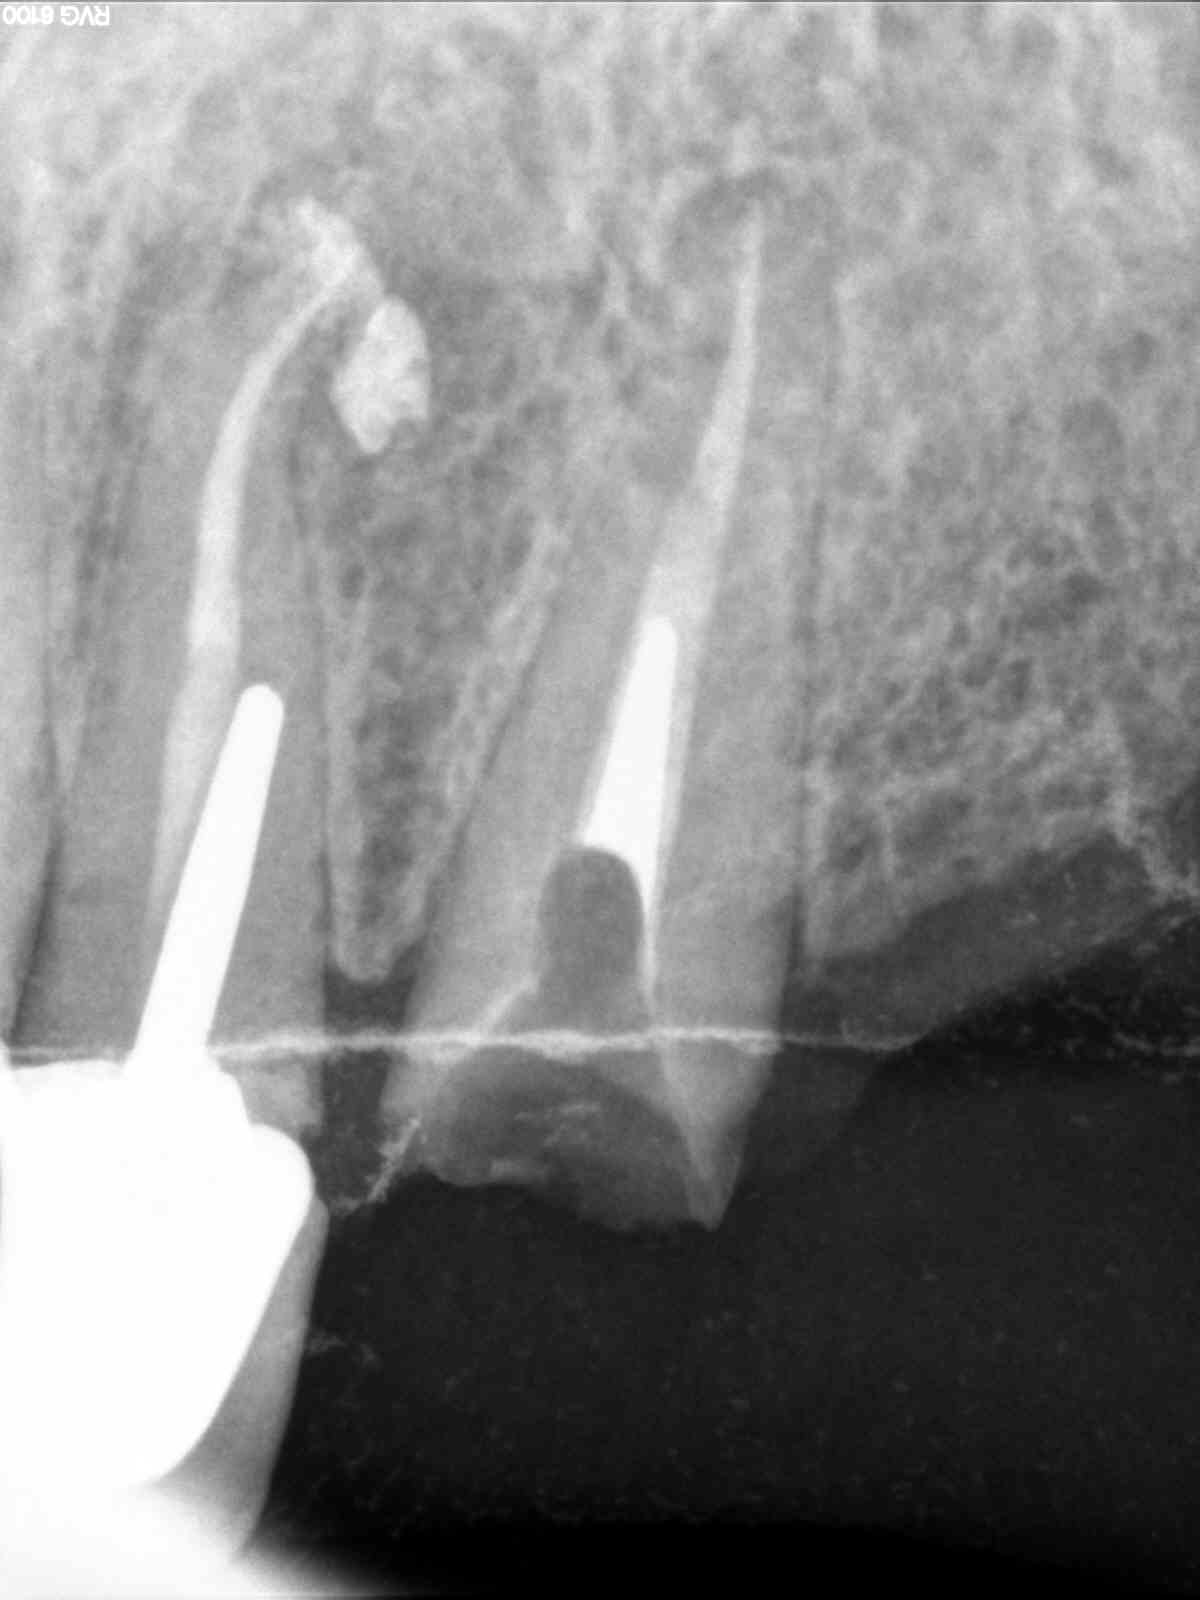

C'est pas faux. Mais avec moult Rx dans différentes incidences tu devrais pouvoir retrouver l'axe à mon avis (avec quelques gouttes de sueur, j'en conviens).

Enfin, merde comme tu dis, courage !

D'après ce qu'on voit sur les Rx j'irais quand même bien enfouir les limites, histoire de cercler au max, il y a de la rétention sur ton IC ? Et les forces vont se répartir d'une drôle de façon sur ton IC et dans le canal :(

Pour moi, il vaudrait mieux prendre 5/10 minutes avec un insert US d'endo pour virer le luxacore et retrouver un bon axe de forage, faire un tenon plus long que de rester dans cette configuration.

Perso je tenterais quand même de virer le reste de luxacore US, voir fraise fine et aides optiques ...

Pas plus tard qu'avant hier, j'ai dégommé quasi 5 mm de métal dans une racine de 23 bien profond à la trans métal et Touati et US (tenon d'un IC pété dans la racine plus bas que ras) alors si j'y arrive ... :)

Edit : me suis appliqué, pas envie de faire un faux canal comme la voisine ;)